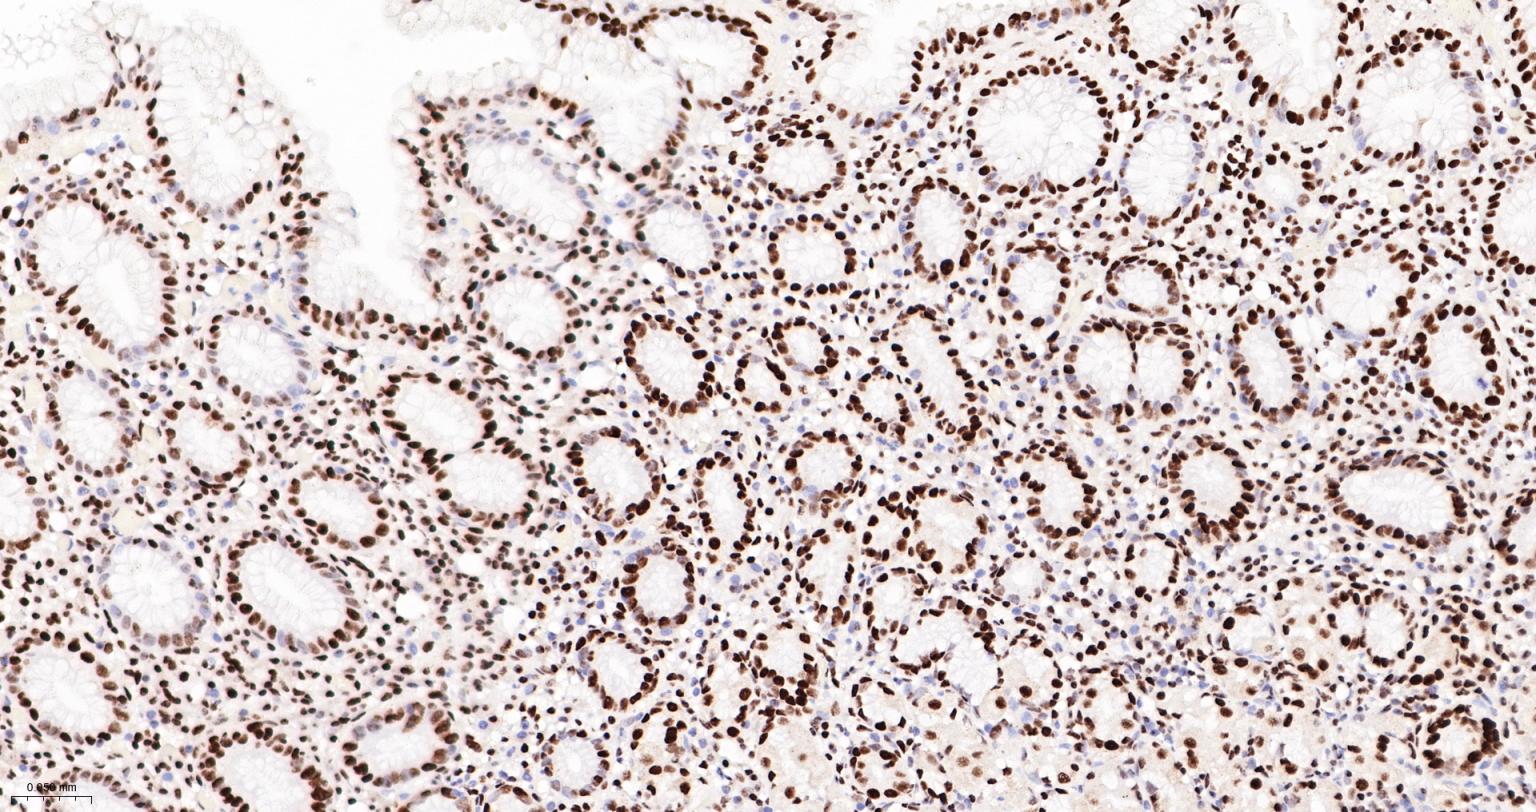

Paraformaldehyde-fixed, paraffin embedded Human Stomach; Antigen retrieval by boiling in sodium citrate buffer (pH6.0) for 15 min; The section was incubated with FUBP1 Monoclonal Antibody, Unconjugated (bsm-60625R) at 1:200 overnight at 4°C, followed by conjugation to the bs-0295G-HRP and DAB (C-0010) staining.

Paraformaldehyde-fixed, paraffin embedded Rat Stomach; Antigen retrieval by boiling in sodium citrate buffer (pH6.0) for 15 min; The section was incubated with FUBP1 Monoclonal Antibody, Unconjugated (bsm-60625R) at 1:200 overnight at 4°C, followed by conjugation to the bs-0295G-HRP and DAB (C-0010) staining.

Paraformaldehyde-fixed, paraffin embedded Mouse Stomach; Antigen retrieval by boiling in sodium citrate buffer (pH6.0) for 15 min; The section was incubated with FUBP1 Monoclonal Antibody, Unconjugated (bsm-60625R) at 1:200 overnight at 4°C, followed by conjugation to the bs-0295G-HRP and DAB (C-0010) staining.